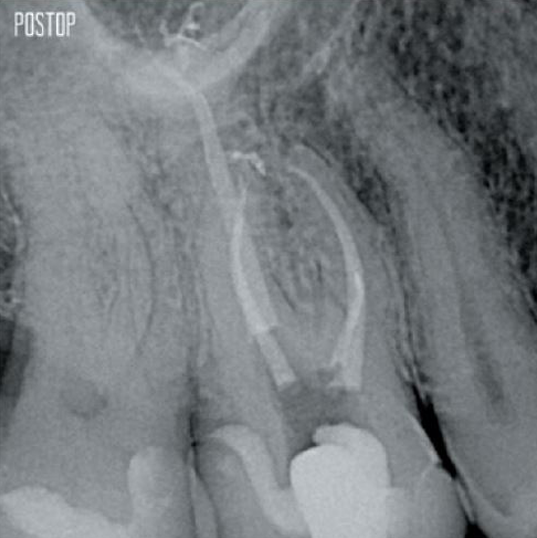

Davantage de dentine préservée. Mise en forme, irrigation et obturation appropriées.

Photos avec l’aimable autorisation du Dr Ahmed Salman